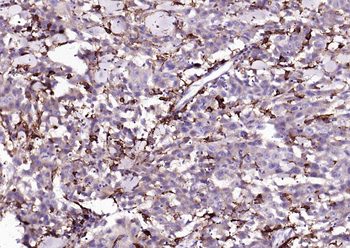

100 μl, 50 μl, 25 μl - Rad51 Recombinant Rabbit Monoclonal Antibody [orb608069]Featured

IF, IHC-Fr, IHC-P, WB

Human, Mouse, Rat

Mouse, Rat

Rabbit

Recombinant

Unconjugated

50 μl, 100 μl - KLF4 Recombinant Rabbit Monoclonal Antibody [orb608075]Featured